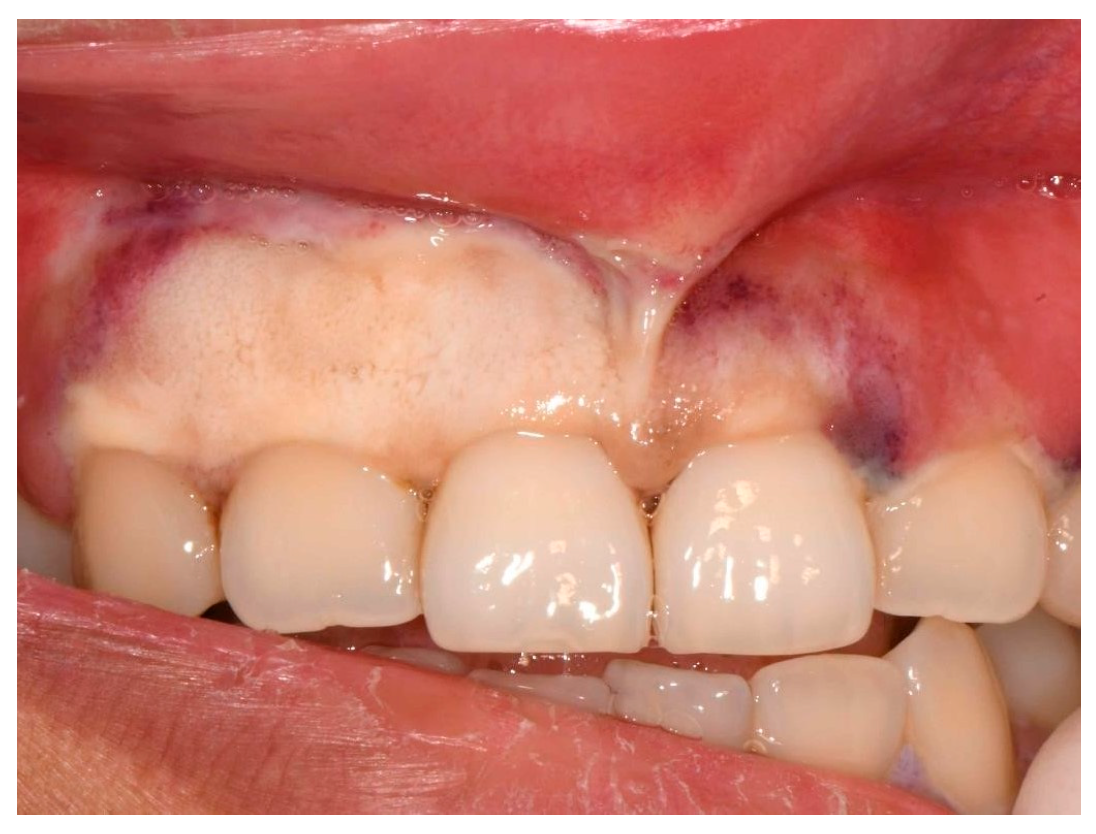

On presentation, the patient reported malaise, odynophagia, abdominal pain, and intermittent nausea and vomiting. Her symptoms started roughly a month before presentation since her return from a developing country and were progressively worsening. At triage, she was noted to be febrile and tachycardic. On examination, we noted bilateral submandibular lymphadenopathy and necrosis of the buccal attached gingiva of the upper anterior region, predominantly from her upper right canine to her upper left central incisor, extending up the upper midline frenum (Figure 1).

Figure 1.

Initial clinical presentation of necrotic buccal attached gingiva (including frenum).